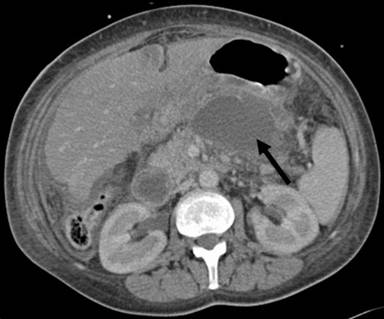

A 40-year-old woman had been admitted for an endoscopic drainage of pseudocyst that developed secondary to gallstone-induced pancreatitis treated elsewhere. The procedure needed to be postponed due to development of a large pulmonary embolus for which the patient was anti-coagulated. As the pseudocyst decreased in size (5 cm diameter) on CT imaging, no drainage was attempted on that admission. Four months later she was re-admitted as an emergency with acute upper abdominal pain and vomiting. On arrival, the patient was unwell, dehydrated and tachycardic. The clinical diagnosis of pancreatitis was confirmed by the raised serum amylase of 203 U/L (reference range: 0-135 U/L). The APACHE II score was 11 (adjusted predicted death rate of 19.6%). Within 12 hours she rapidly deteriorated, developed type I respiratory failure and required respiratory support. The contrast CT revealed that the known pseudocyst had increased in size, measuring 11.7x5.0 cm with features of pancreatic necrosis (Figure 1) and large bilateral pleural effusions. It extended into the posterior mediastineum around the oesophagus. Bilateral chest drains were inserted and ionotropic cardiac support implemented. At this stage her APACHE II score was calculated at 20 (adjusted predicted death rate of 47.6%). Since the patient continued to deteriorate, endotracheal ventilation became necessary. Immediately after insertion of the endotracheal tube, 2 L of amylase rich fluid (26,562 U/L) spontaneously drained via the tube. The diagnosis of a pancreaticobronchial fistula was confirmed on the repeated contrast CT (7 days after the admission), which showed a large amount of gas inside the cyst and evidence of fistulation into the right lower lobe bronchi (Figures 2 and 3). The pseudocyst was drained percutaneously under the CT guidance via the transgastric route and the pleural collections by bilateral chest tubes (amylase: 13,995 U/L). Subsequent tubogram and bronchoscopy did not confirm the fistulous connection with the bronchial tree. Subsequently, 16 days following the admission, due to progressive deterioration, the patient underwent an open pancreatic necrosectomy. Intraoperatively, the pancreatic collection was tracking cranially towards the diaphragm. With every lung inflation by the ventilator air was seen to escape from the peripancreatic collection indicating a communication with the airway. Therefore, following debridement of the peripancreatic tissues, an underwater-seal drain was inserted into the cavity. Four days after the necrosectomy the woman was weaned off the ventilator and the air leak in the under water seal drain ceased within the next 5 days. The abdominal drains were removed on the 11th postoperative day. The patient returned to the surgical ward after 4 weeks of intensive therapy unit (APACHE II score 1, adjusted predicted death rate 5.4%) and following a prolonged period of convalescence, was discharged home 2 months later. The open drainage of the cyst and the pleural collections combined with supportive measures such as intravenous octreotide infusion and parental nutrition (L-alanyl-L-glutamine-supplemented parental nutrition) for 24 days resulted in the successful recovery.

Figure 1. CT scan at admission showing pancreatic necrosis and a large pseudocyst (arrowed). |